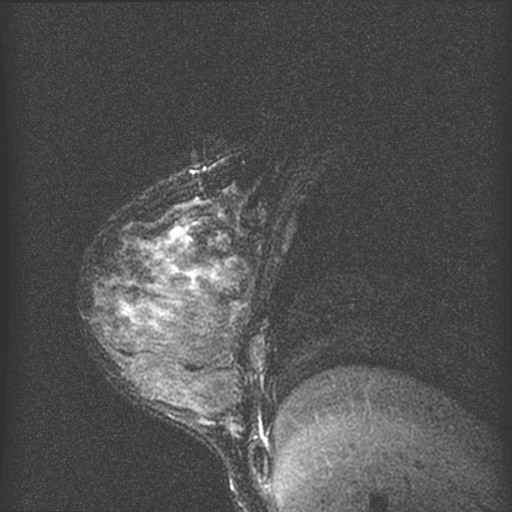

borst